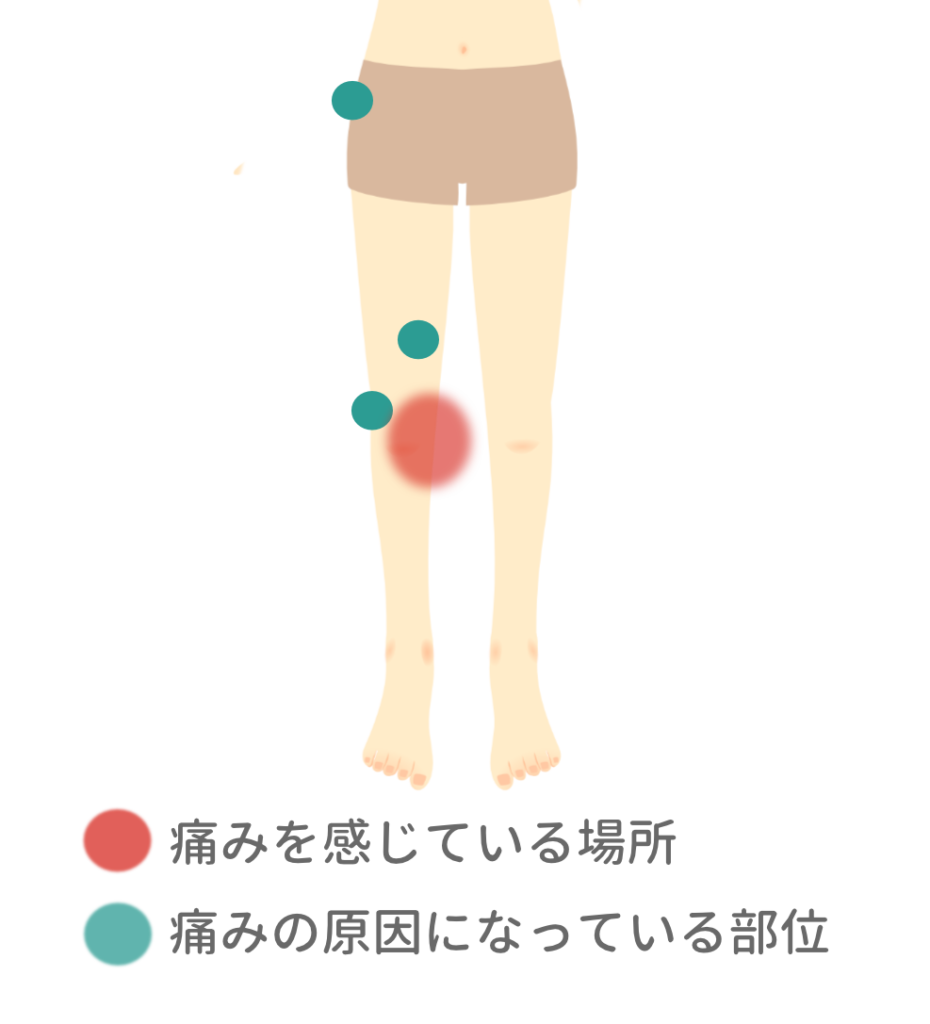

- 痛む場所と痛みの原因になっている部位をチェック

痛む場所と痛みの原因になっている部位をチェック

痛む場所をチェック

痛みのある場所=痛みの原因とはかぎりません。

痛みの原因になっている部位をチェック

痛みの原因になっている部位を指で押すと「ズーン」とした響きが出ることも。